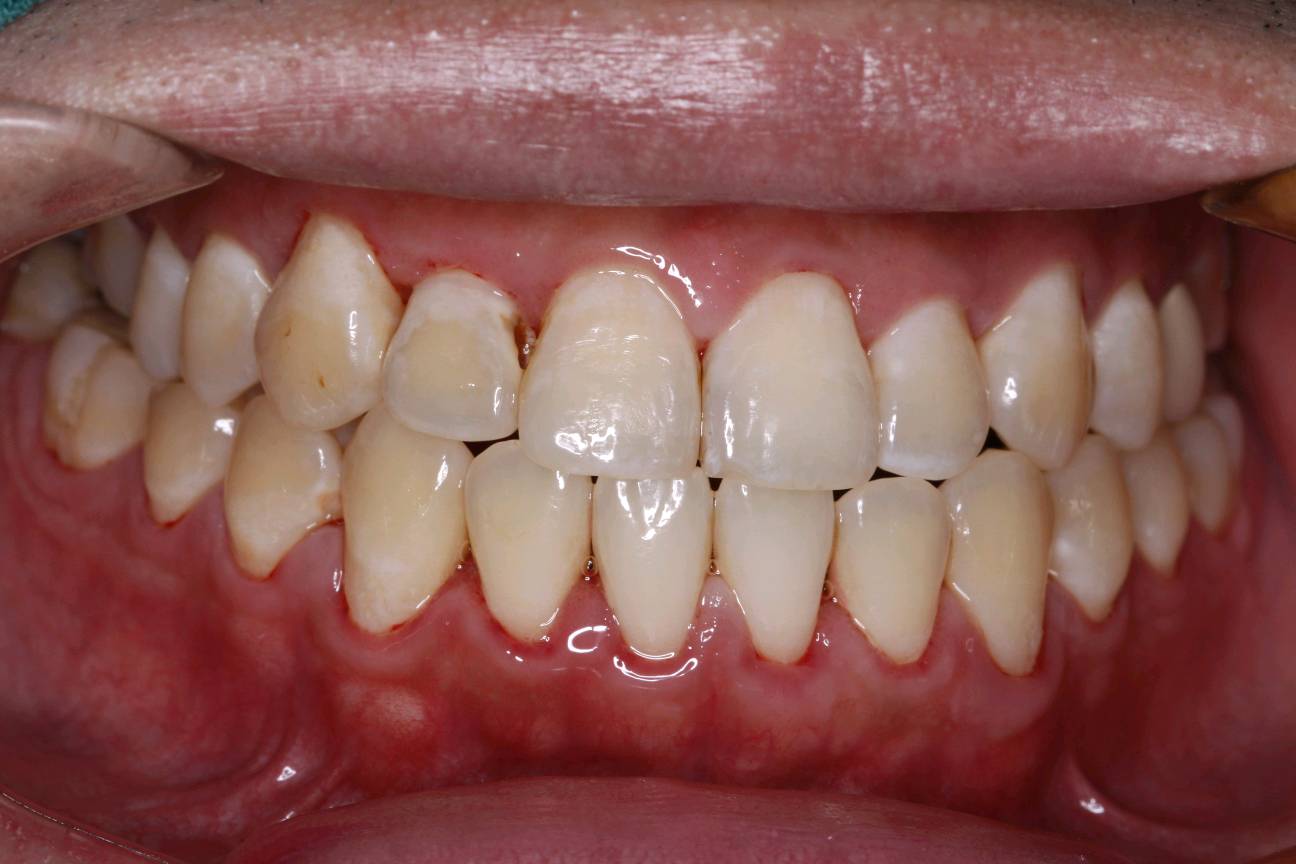

患者男三十岁,12近中邻面龋坏,经常性食物嵌塞,探+-,扣-,冷水入洞一过性敏感。牙面色泽偏黄,牙颈部呈白垩色。余无特殊。治疗计划:去腐+复合树脂充填+贴面修复。如果偶感食物嵌塞,还是要到口腔诊所及时就医检查。很有可能是发生龋坏,需要及时修复,如果出现疼痛的现象,就不能靠单纯的补牙修复那么简单了。所以每半年定期检查牙齿,才能避免出现严重的口腔疾病。通过西诺德口扫系统,3D打印口腔模型。当天上午备牙 下午即可佩戴。色泽形态自然,边缘密合,患者满意!

术中